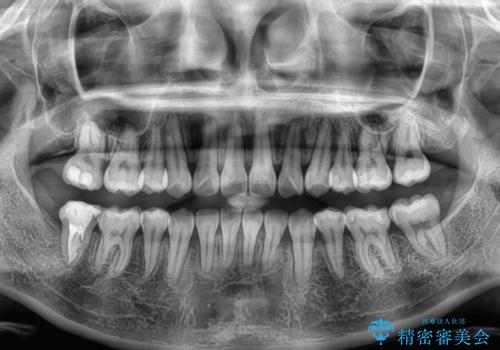

上下の八重歯とクロスバイト ワイヤー装置での抜歯矯正

20歳ということもあり、歯の移動速度が非常に速く、1年強という短期間であっという間に治療を終えることができました。